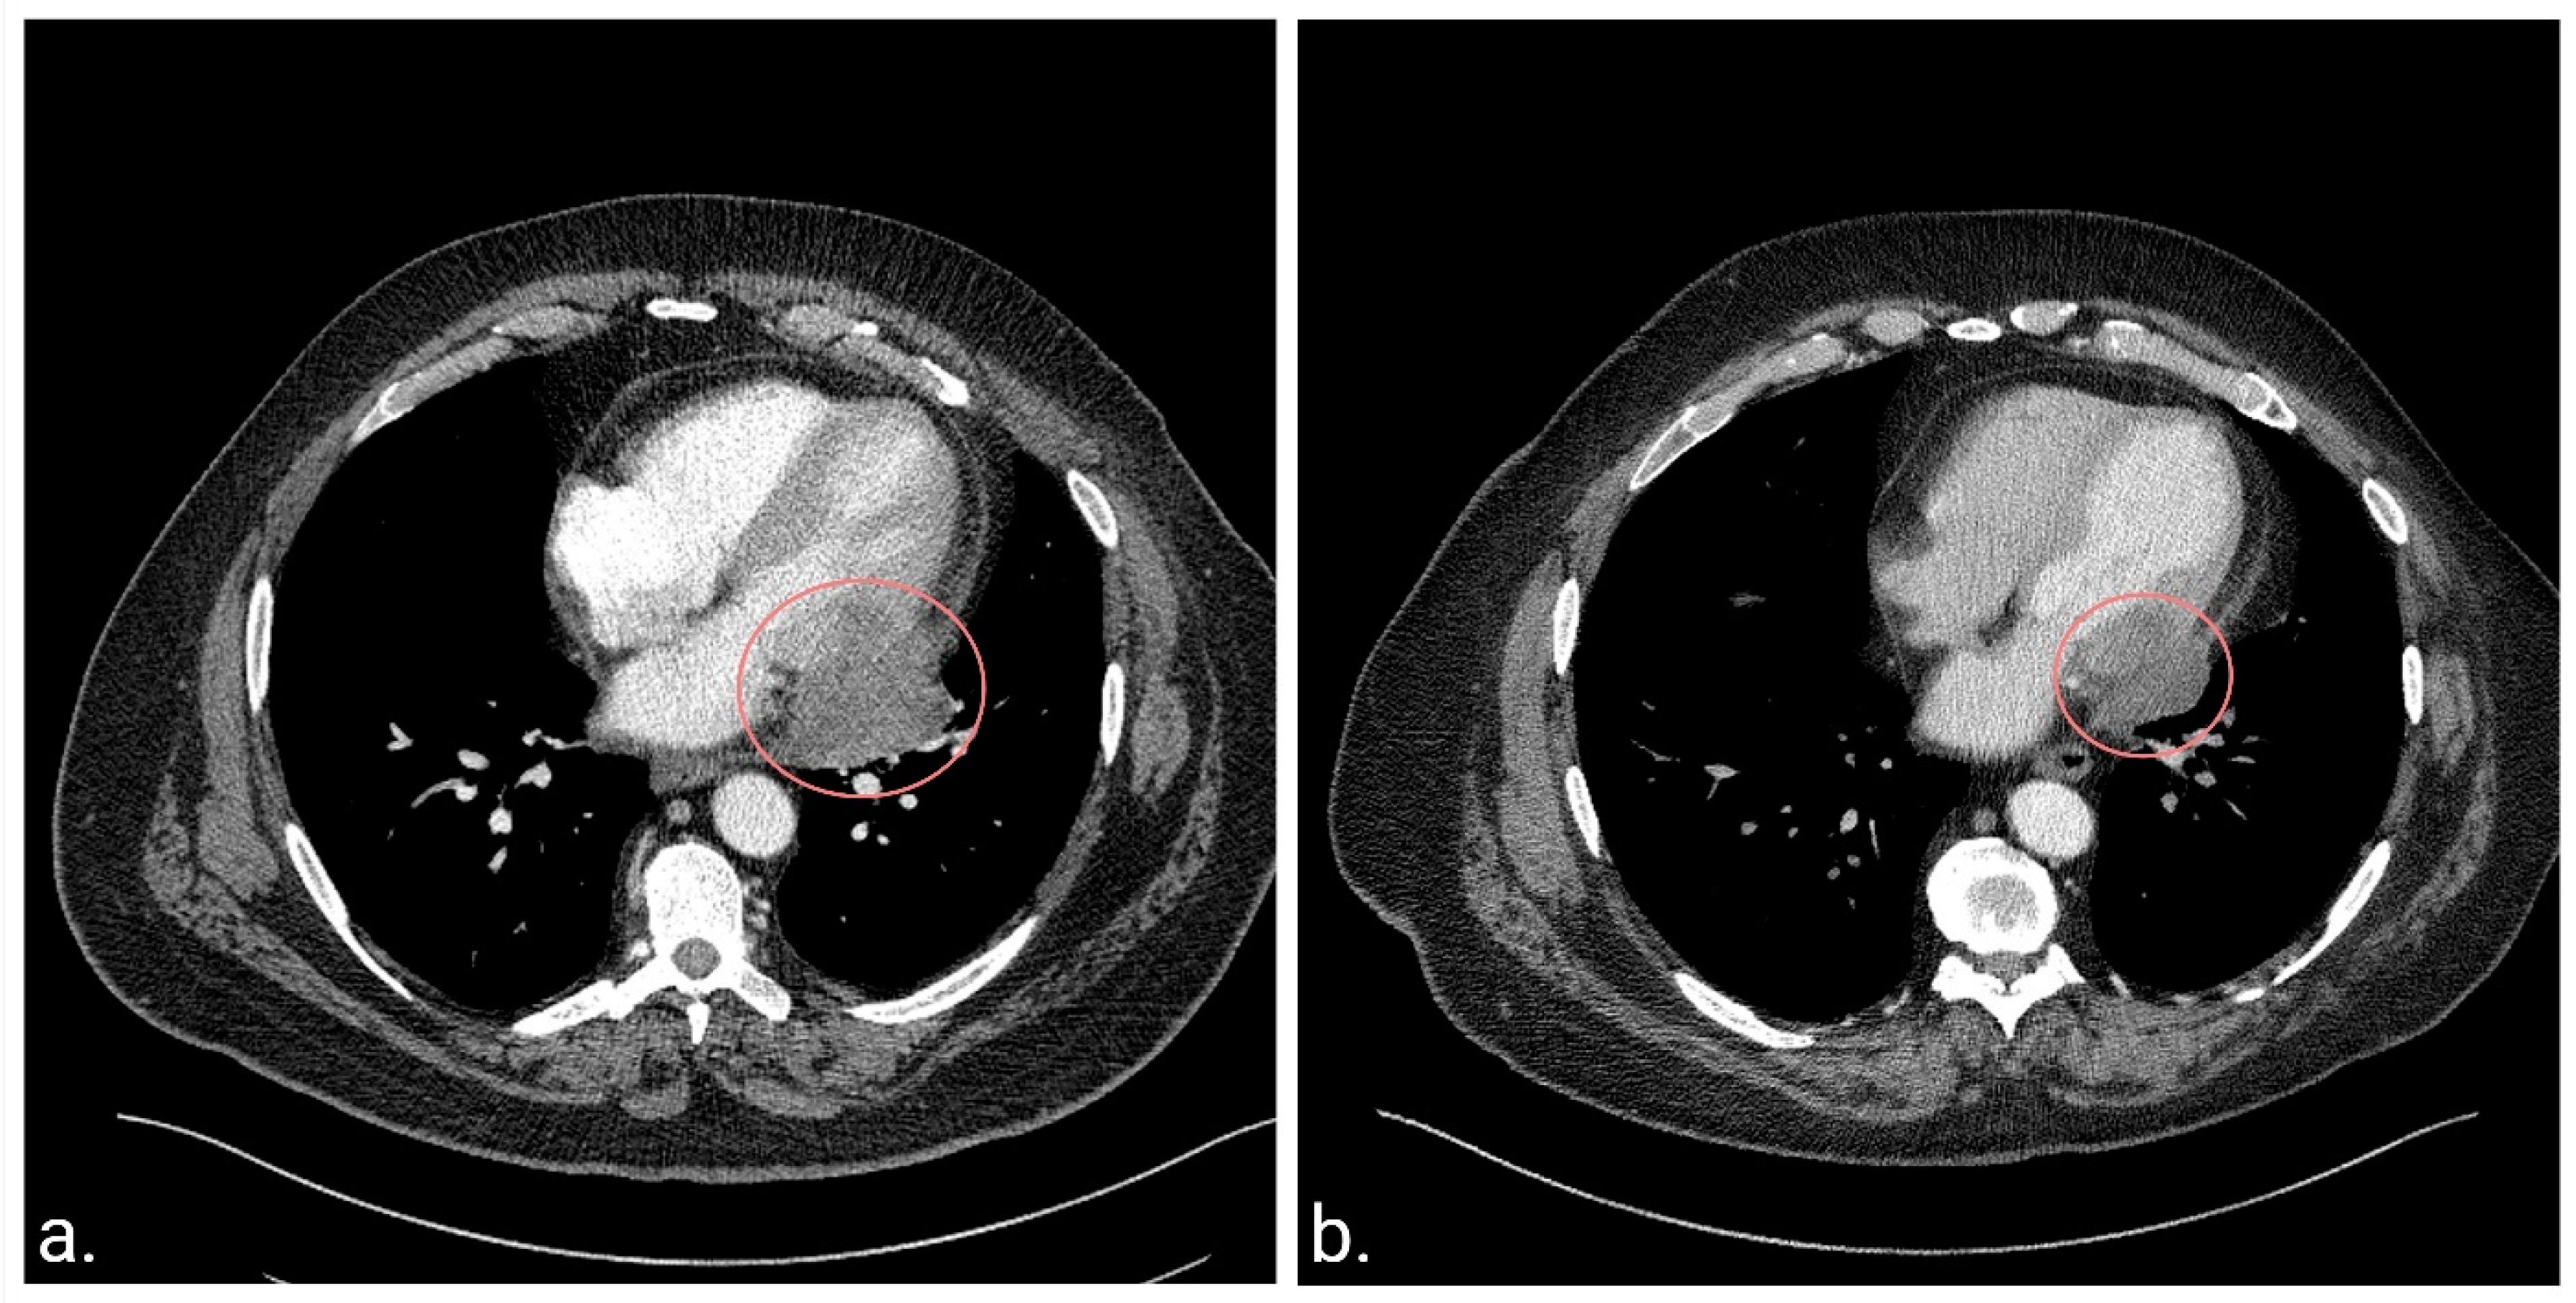

2. Case Report